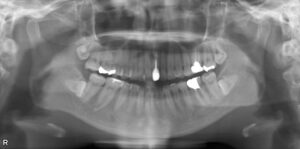

上下4本欠損症例

BEFORE AFTER 62歳男性/上下4本欠損/インプラント埋込手術 【治療内容】 上顎前歯の欠けが主訴でご来院の患…